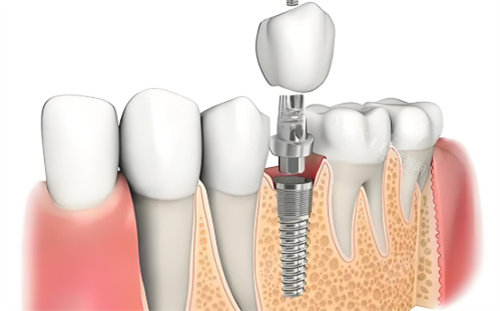

卡尔斯种植牙采用4级冷作钛材质,这种材料具有良好的生物相容性。其表面经过改良的SLA工艺处理,形成微米级粗糙表面,有利于骨组织结合。双向螺旋式切刃设计是该产品的特色之一,这种结构有助于提高初期稳定性,同时能加速骨结合过程。

ITI(士卓曼)种植体在材料选择上更为多样化,包括纯钛和钛锆合金等不同材质。表面处理技术是其一大亮点,如SLActive亲水表面技术能够促进早期骨结合,缩短愈合时间。部分特殊型号的设计特别适合骨量不足的情况或即刻种植的需求。